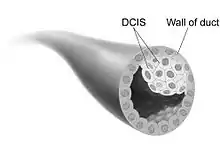

Ductal carcinoma in situ (DCIS), also known as intraductal carcinoma, is a pre-cancerous or non-invasive cancerous lesion of the breast.[1][2] DCIS is classified as Stage 0.[3] It rarely produces symptoms or a breast lump one can feel, typically being detected through screening mammography.[4][5] It has been diagnosed in a significant percentage of men (see male breast cancer).[6]

In DCIS, abnormal cells are found in the lining of one or more milk ducts in the breast. In situ means "in place" and refers to the fact that the abnormal cells have not moved out of the mammary duct and into any of the surrounding tissues in the breast ("pre-cancerous" refers to the fact that it has not yet become an invasive cancer). In some cases, DCIS may become invasive and spread to other tissues, but there is no way of determining which lesions will remain stable without treatment, and which will go on to become invasive.[7] DCIS encompasses a wide spectrum of diseases ranging from low-grade lesions that are not life-threatening to high-grade (i.e. potentially highly aggressive) lesions.

DCIS has been classified according to the architectural pattern of the cells (solid, cribriform, papillary, and micropapillary), tumor grade (high, intermediate, and low grade), the presence or absence of comedo histology,[8] or the cell type forming the lesion in the case of the apocrine cell-based in situ carcinoma, apocrine ductal carcinoma in situ.[9] DCIS can be detected on mammograms by examining tiny specks of calcium known as microcalcifications. Since suspicious groups of microcalcifications can appear even in the absence of DCIS, a biopsy may be necessary for diagnosis.